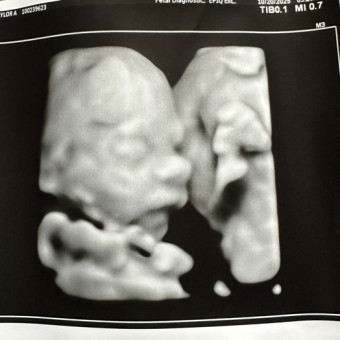

We’re so excited to meet our baby girl soon, and we’re so grateful you’re celebrating her with us! Her nursery will be filled with soft wildflower vibes — colorful, cozy, and all things sweet and simple. 🌼🌸